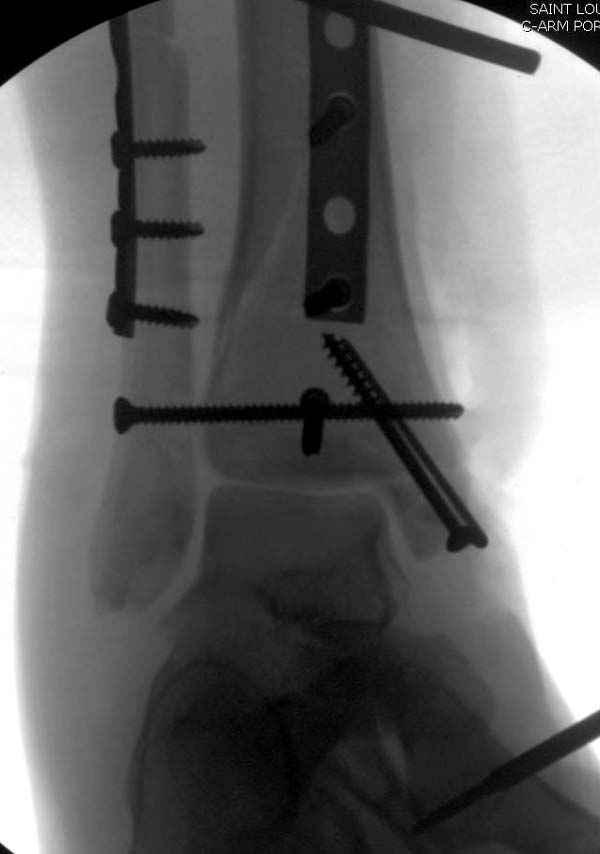

Из заднего доступа остеотомия тонким остеотомом и коррекции на ЭОПе.

Без применения сложной конструкции, а обычными параллельными шурупами. Шурупы в 3.5 мм и дополнительно фиксация крючковидной пластиной, сделанной из 3.5 mm semitubular пластиной, Butress или аntiglade фиксация.

Здесь алгоритм фиксации свежего перелома и преоперационный план для обсуждаемого случая.